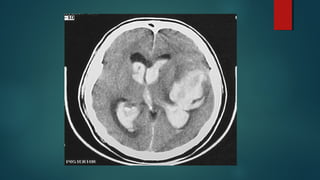

Este documento es el programa para un taller de imágenes del curso de emergencia 2015 impartido por el Dr. Víctor Delgado. El taller se centra en el uso de imágenes médicas para el diagnóstico y tratamiento de pacientes en coma traumático según la base de datos de Marshall. El Dr. Delgado es el único instructor repetido a lo largo del documento.